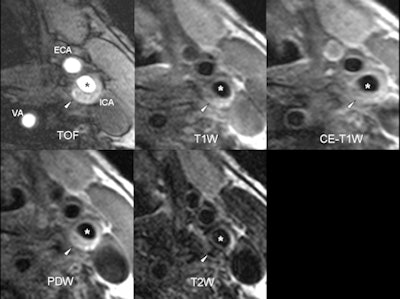

| Axial MR images of an 82-year-old symptomatic patient without cardiovascular risk factors. The patient suffered a stroke ipsilateral to the left carotid artery five days before the MRI examination. The arrowhead points to a complicated eccentric plaque that is hyperintense on time-of-flight (TOF) and T1-weighted images, indicative of intraplaque hemorrhage. Of note, no luminal stenosis in the ICA (asterisk) can be seen. The images illustrate that cerebrovascular events due to macroangiopathic carotid disease can occur in the absence of luminal stenosis. ICA = internal carotid artery, ECA = external carotid artery, VA = vertebral artery, PDW = proton density-weighted image. (Provided by Dr. Tobias Saam) |

"Vessel wall imaging is an exciting field which has entered clinical practice, and its role will grow. Luminal stenosis alone is insufficient to predict plaque vulnerability," said Prof. Maximilian Reiser, director of clinical radiology at Ludwig Maximilian University, former European Congress of Radiology (ECR) and European Society of Radiology (ESR) president, and chair of today's New Horizons session. "It is mandatory for radiologists to know more about new opportunities which will be increasingly used in practice."

One of the main problems with vessel wall techniques is that often the only imaging criteria employed to indicate an intervention is the degree of stenosis, regardless of plaque composition. Biological processes such as positive remodeling mean that risky plaques without stenosis may still result in cardiac or cerebral events. In fact, of the ischemic strokes due to atherosclerotic disease, only 10% are watershed infarcts with a high degree of carotid stenosis, whereas 90% of ischemic strokes are caused by thrombosis and distal embolization due to plaque rupture.

"The higher the stenosis, the more likely the existence of a complicated plaque," Saam explained. "However, studies have shown that the majority of myocardial infarctions occur in vessels with less than 50% stenosis. Little is known of the prevalence and the impact of complicated plaques in acute stroke patients without carotid stenosis."